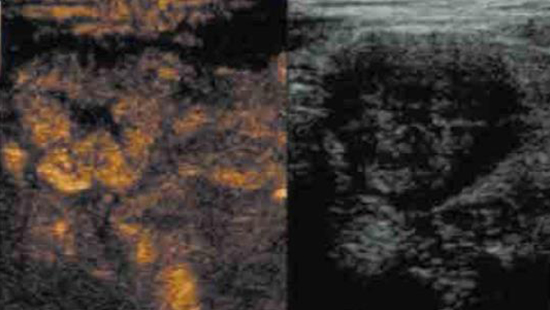

Une échographie de contraste peut être réalisée pour visualiser les segments inflammatoires de la paroi du côlon. Son importance dans le diagnostic des maladies inflammatoires chroniques de l’intestin est le sujet des recherches scientifiques actuelles. Pour l’heure, il semble qu’elle puisse améliorer l’évaluation de l’activité de la maladie4 .

En outre, la procédure semble faciliter la différenciation entre les sténoses inflammatoires et les sténoses fibreuses, car l’absorption de l’agent de contraste est plus importante dans les premières que dans les secondes8,10. L’échographie de contraste est très utile pour différencier la formation d’un abcès et l’inflammation9. Dans la première, il y a une absence notable d’agent de contraste dans la zone de l’abcès après l’administration, alors que la perfusion est visible dans le tissu inflammatoire9. Elle peut également être utilisée pour visualiser l’intégralité d’une fistule lorsque l’agent de contraste est injecté dans le trajet fistulaire. Dans un avenir proche, l’utilisation de l’échographie de contraste de l’intestin deviendra certainement plus répandue à mesure que l’expérience et l’évaluation clinique se développeront. Pour réaliser une CEUS, l’agent de contraste est injecté via un cathéter veineux cubital, suivi de sérum physiologique10.

Les caractéristiques de perfusion sont ensuite évaluées instantanément pendant l’examen.

Exemple d’image : modifications pariétales inflammatoires aiguës avec un aflux important d’agent de contraste (augmentation de la perfusion dans le cadre de l’inflammation aiguë)

Exemple d’image : Maladie de Crohn d’évolution fibreuse chronique et réponse inadéquate au traitement médicamenteux : faible absorption d’agent de contraste après application)